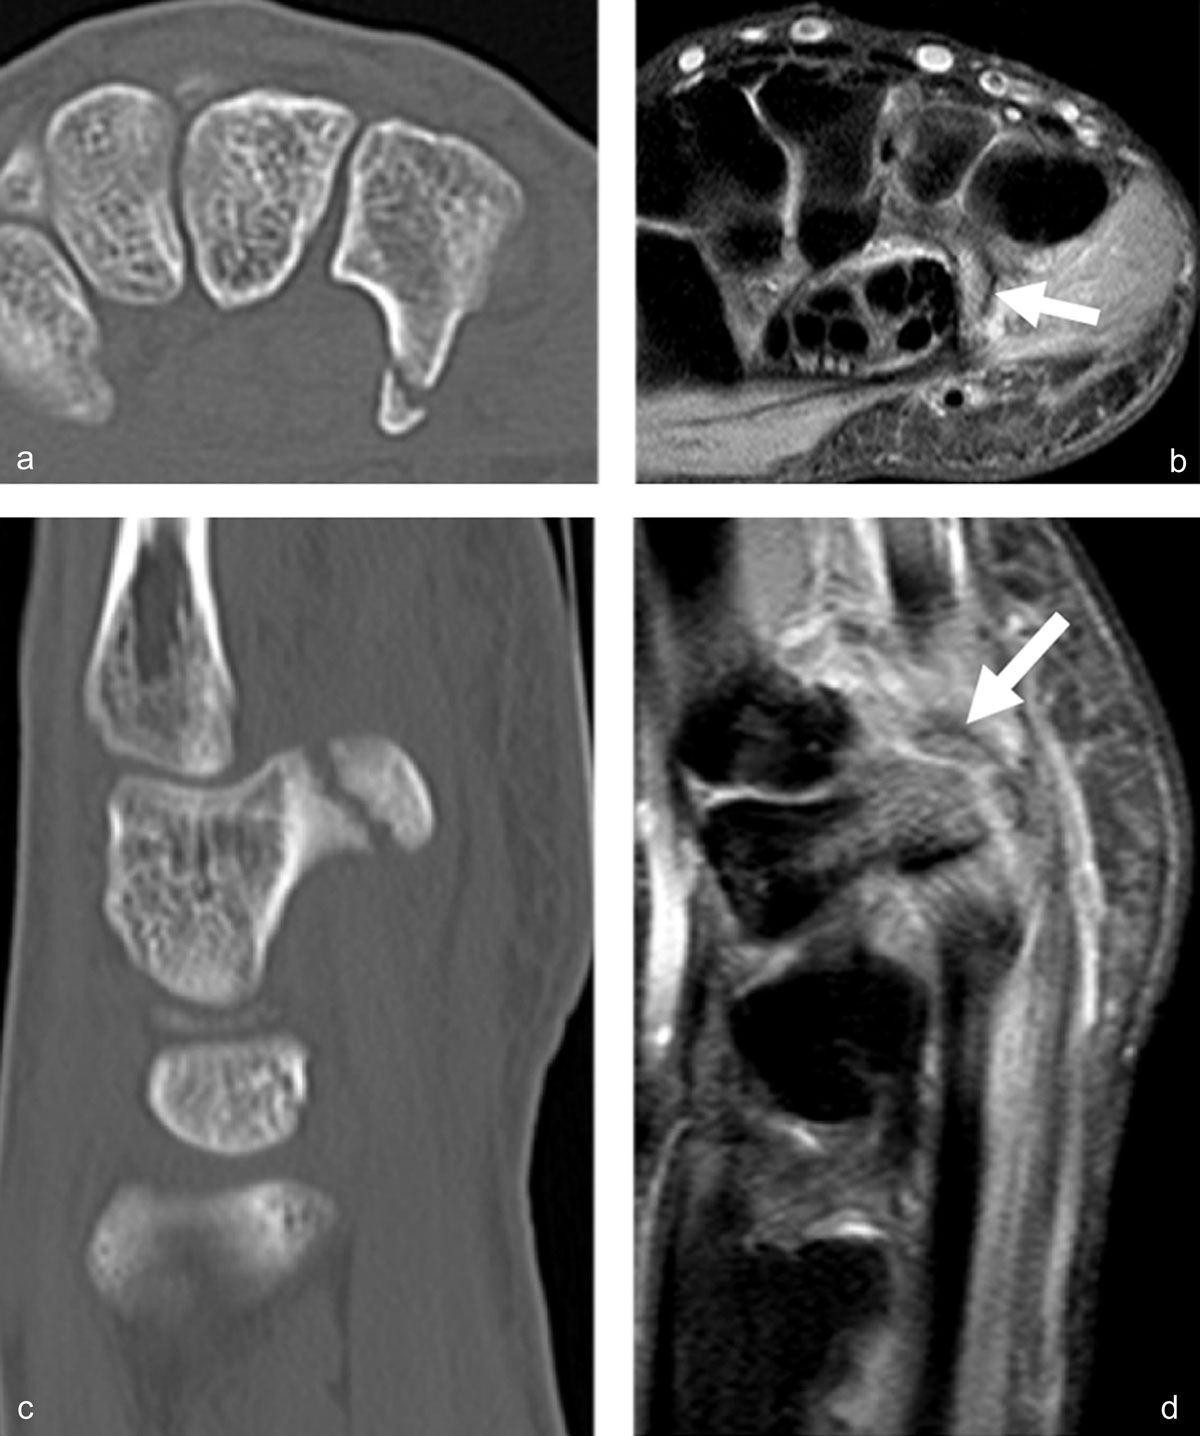

Figure 7

Another case of direct compression of the hook of the hamate. Axial CT (a) and sagittal reconstruction (c) disclose the avulsion fracture, much easier than the corresponding axial (b, arrow) and sagittal (d, arrow) proton-density fat-saturated MR images.